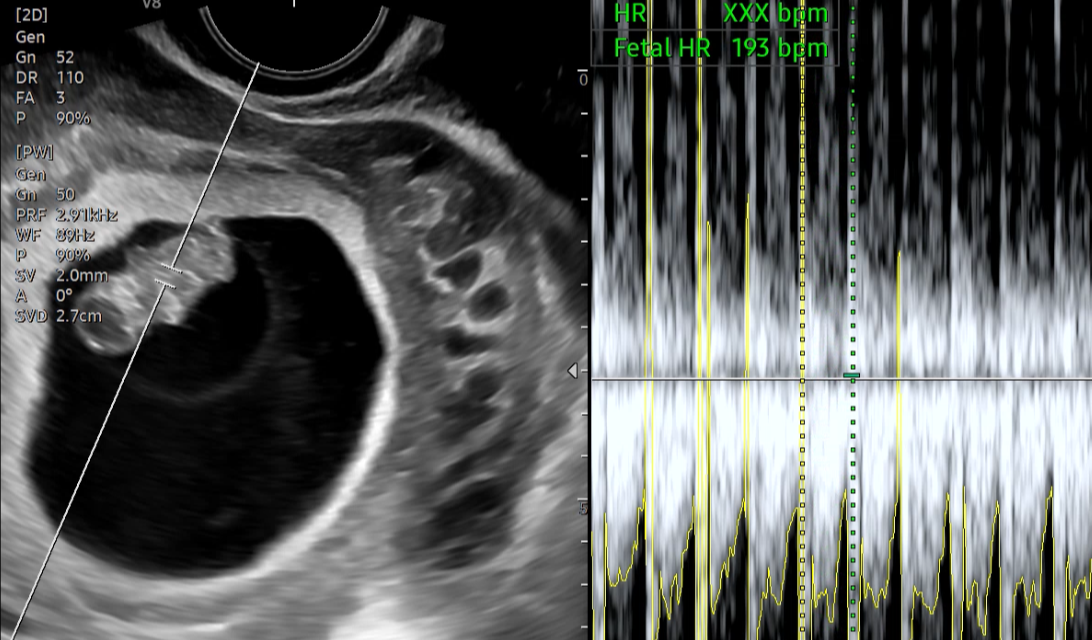

제일 귀여운 형태를 볼 수 있다고 하는 9주예요. 이때 가면 젤리곰을 볼 수 있거든요😊

2주 사이에 팔이랑 다리처럼 보이는 무언가의 형태가 생겼어요. 꼬물꼬물

이제는 몸길이도 젤 수 있습니다ㅎㅎ 귀여워☺️ 이때 추추의 길이는 2.13센티네요.

심박수는 193 bpm.. 평균 심박수보다 조금 빠르다고 선생님께서 집에서 많이 쉬라고 하셨어요.

첫째랑 맨날 하원하고 놀이터에서 같이 놀다 보니 무리를 해서 그랬나 생각이 많아졌습니다.🥲

(심박수가 빠른 원인 중에 하나가 심장이나 갑상선에 문제가 있어서 그렇다 하셨는데, 저는 갑상선에 문제가 없기 때문에 갑상선 문제는 아닐 것 같다 하셨습니다.. 다음 검진 때 초음파를 보자 하셨어요.)